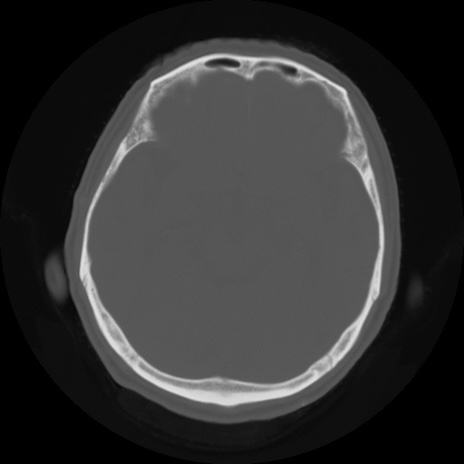

【頭部】症例5 CT(横断像)

【症例】80歳代 男性

【主訴】頭部打撲

【現病歴】外出先で椅子から立ち上がる際に、つまづいて後方へ転倒し受傷。転倒時に意識はあった。

【身体所見】BP 217/71、HR 96、JCS1-1、 難聴あり、顔色良好、右後頭部に擦過創あり。神経学的異常なし。

症例5の画像所見と診断は?